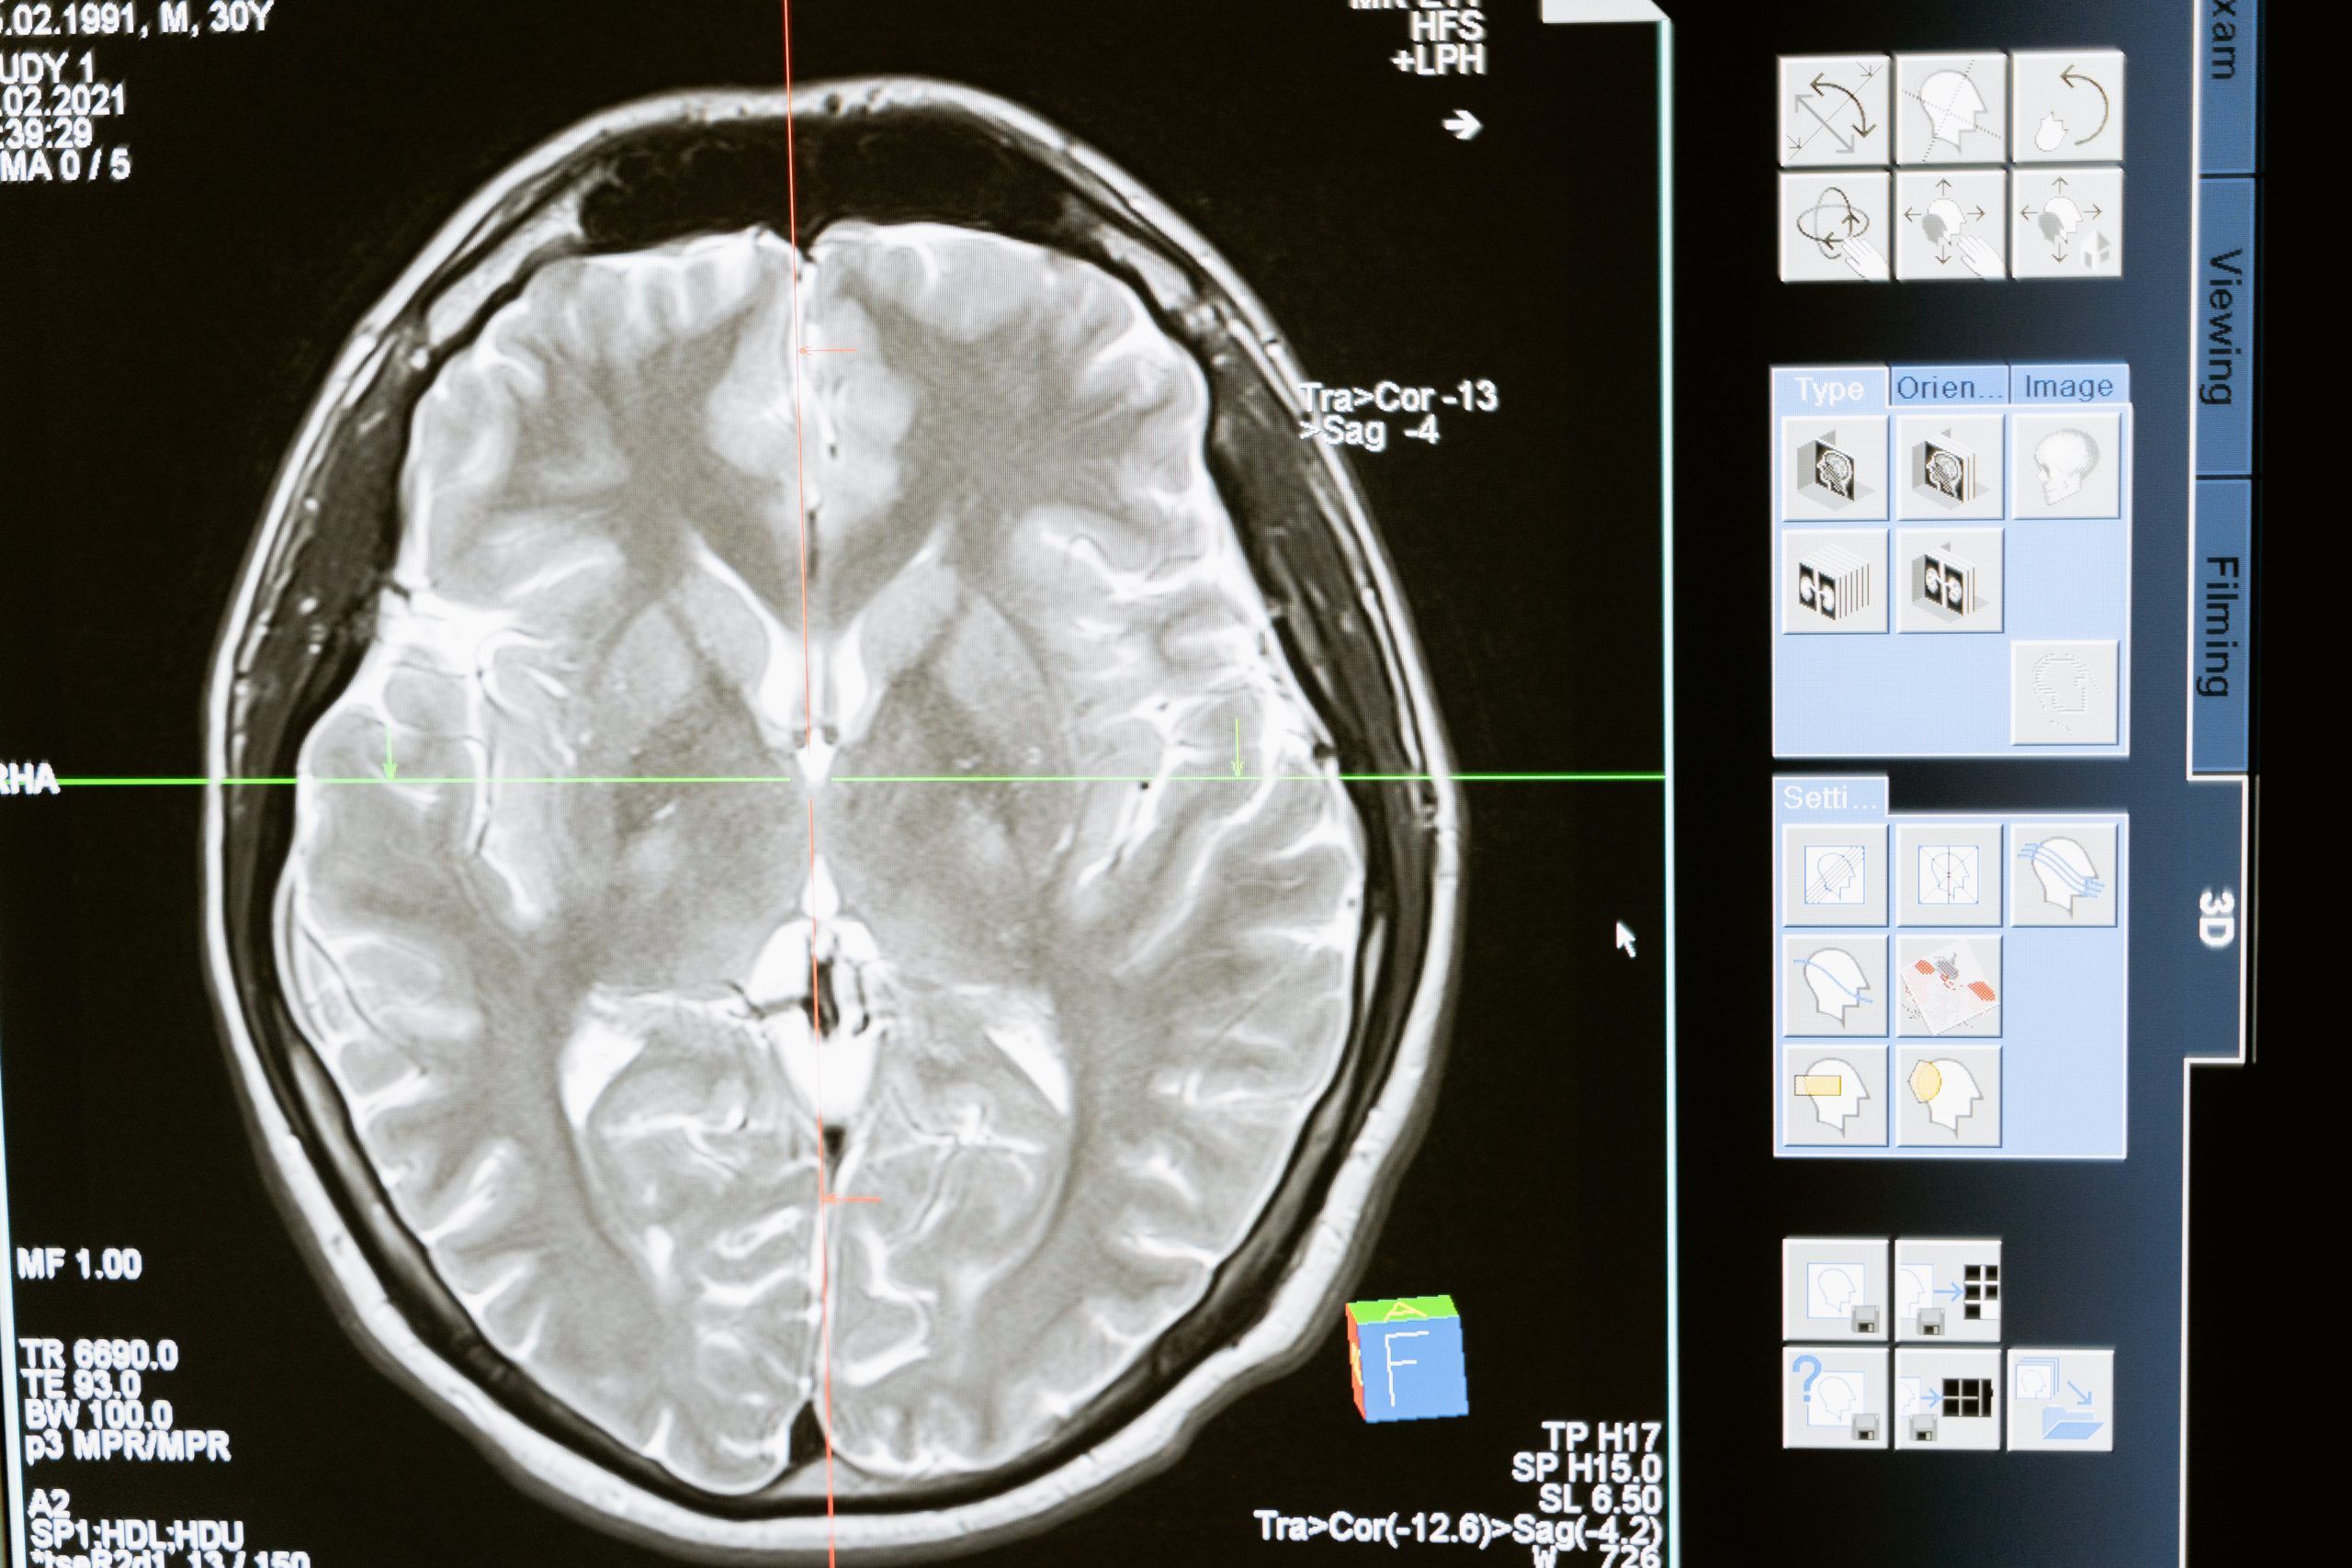

Najveća proteinska mapa tumora, analizirana uz pomoć umjetne inteligencije, omogućila je otkrivanje tajne zbog koje je toliko teško pronaći oružje koje može pobijediti najagresivniji tumor mozga, glioblastom, za koji je danas stopa preživljavanja ima samo godinu dana i opire se liječenju. ‘Trik’ je u tome što stanice ovog tumora bježe od imunološkog sustava i lijekova jer se transformiraju oponašajući zdrave neurone. Oni se maskiraju do te mjere da pružaju svoje ‘pipke’ (aksone) kako bi se povezali sa zdravim moždanim stanicama.

U slučaju glioblastoma karta je dobivena na temelju uzoraka uzetih od 123 pacijenta u trenutku dijagnoze i u relapsu koji se pojavio nakon terapije; razmatrane su i promjene izazvane u proteinima prisutnošću enzima. Ovaj pristup, dodaje Iavarone, “pruža pregled mogućih promjena tumora na individualnoj razini koji je nemoguće dobiti samo genetskom analizom”. Na taj je način također bilo moguće otkriti slabu točku tumora.